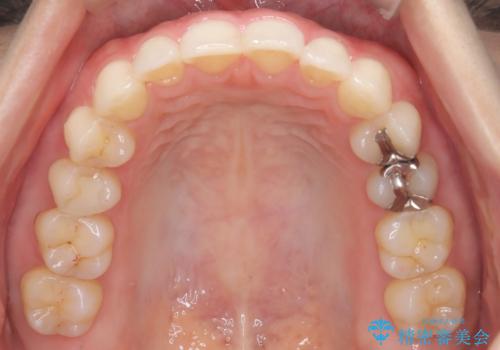

- 下顎前歯の叢生を主訴に来院されました。

臼歯関係の状態から下顎前歯一本の抜歯を行う治療計画を立て、インビザラインを使用して治療を行いました。

今回の抜歯ケースはインビザラインでも綺麗に治ります。